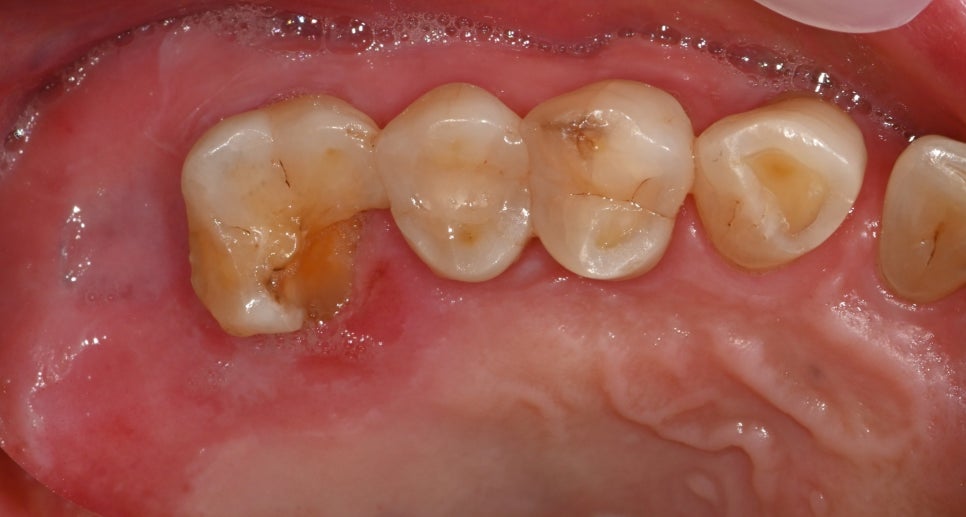

The examination results showed not a simple cavity or crown fracture, but cracks extending to the root area.

If the crack extends to the root tip, it is difficult to save the tooth with conservative treatment,

and extraction followed by implant treatment should be considered.

The crack had spread to the root area, so the tooth could not be left in place.